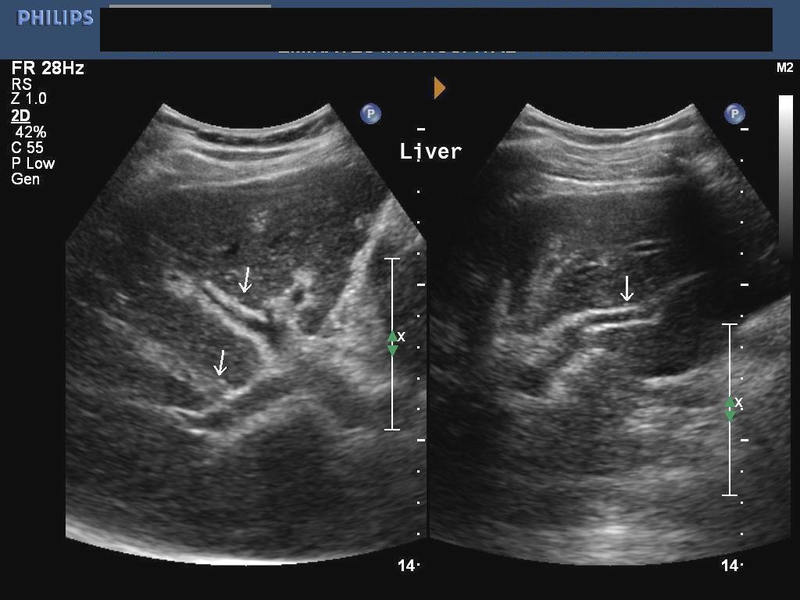

Liver/ Spleen involvement in Schistosomiasis

his patient is a known case of Bilharziasis and ultrasound showed hepatosplenomegaly with increased echogenicity of the periportal regions of the portal veins suggesting periportal fibrosis. Fibrosis of the periportal regions of the liver is a known complication of hepatic involvement in schistosomiasis. Ultrasound images are courtesy of Ravi Kadasne, MD, UAE.